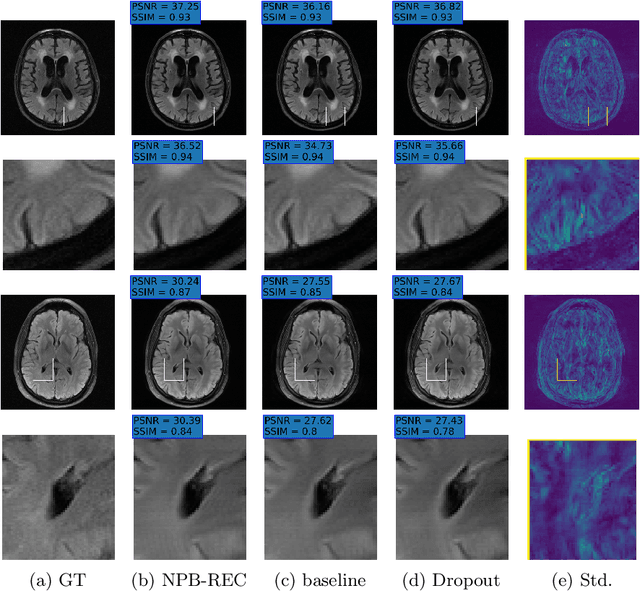

Abstract:The ability to reconstruct high-quality images from undersampled MRI data is vital in improving MRI temporal resolution and reducing acquisition times. Deep learning methods have been proposed for this task, but the lack of verified methods to quantify the uncertainty in the reconstructed images hampered clinical applicability. We introduce "NPB-REC", a non-parametric fully Bayesian framework, for MRI reconstruction from undersampled data with uncertainty estimation. We use Stochastic Gradient Langevin Dynamics during training to characterize the posterior distribution of the network parameters. This enables us to both improve the quality of the reconstructed images and quantify the uncertainty in the reconstructed images. We demonstrate the efficacy of our approach on a multi-coil MRI dataset from the fastMRI challenge and compare it to the baseline End-to-End Variational Network (E2E-VarNet). Our approach outperforms the baseline in terms of reconstruction accuracy by means of PSNR and SSIM ($34.55$, $0.908$ vs. $33.08$, $0.897$, $p<0.01$, acceleration rate $R=8$) and provides uncertainty measures that correlate better with the reconstruction error (Pearson correlation, $R=0.94$ vs. $R=0.91$). Additionally, our approach exhibits better generalization capabilities against anatomical distribution shifts (PSNR and SSIM of $32.38$, $0.849$ vs. $31.63$, $0.836$, $p<0.01$, training on brain data, inference on knee data, acceleration rate $R=8$). NPB-REC has the potential to facilitate the safe utilization of deep learning-based methods for MRI reconstruction from undersampled data. Code and trained models are available at \url{https://github.com/samahkh/NPB-REC}.

Abstract:Uncertainty quantification in deep-learning (DL) based image reconstruction models is critical for reliable clinical decision making based on the reconstructed images. We introduce "NPB-REC", a non-parametric fully Bayesian framework for uncertainty assessment in MRI reconstruction from undersampled "k-space" data. We use Stochastic gradient Langevin dynamics (SGLD) during the training phase to characterize the posterior distribution of the network weights. We demonstrated the added-value of our approach on the multi-coil brain MRI dataset, from the fastmri challenge, in comparison to the baseline E2E-VarNet with and without inference-time dropout. Our experiments show that NPB-REC outperforms the baseline by means of reconstruction accuracy (PSNR and SSIM of $34.55$, $0.908$ vs. $33.08$, $0.897$, $p<0.01$) in high acceleration rates ($R=8$). This is also measured in regions of clinical annotations. More significantly, it provides a more accurate estimate of the uncertainty that correlates with the reconstruction error, compared to the Monte-Carlo inference time Dropout method (Pearson correlation coefficient of $R=0.94$ vs. $R=0.91$). The proposed approach has the potential to facilitate safe utilization of DL based methods for MRI reconstruction from undersampled data. Code and trained models are available in \url{https://github.com/samahkh/NPB-REC}.